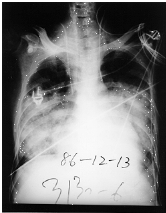

15. 一60公斤之70歲男性以前並無肺部毛病,三天前因胃癌手術,突然發生呼吸困難,胸部X光如圖所示,動脈血氣體分析如下:pH:7.48,PaCO2:30 mmHg,PaO2:55 mmHg,HCO3-:22 mEq/L (經鼻管氧氣FiO2:40%),血壓130/70 mmHg,心跳100次/分,體溫37℃,肺動脈楔壓為16 mmHg,此病人最可能之診斷為何? (A) 急性心因性肺水腫 (B) 術後肺動脈栓塞症 (C) 急性呼吸窘迫症候群 (D) 腹部手術後引起之肺塌陷(atelectasis) (E) 吸入性肺炎